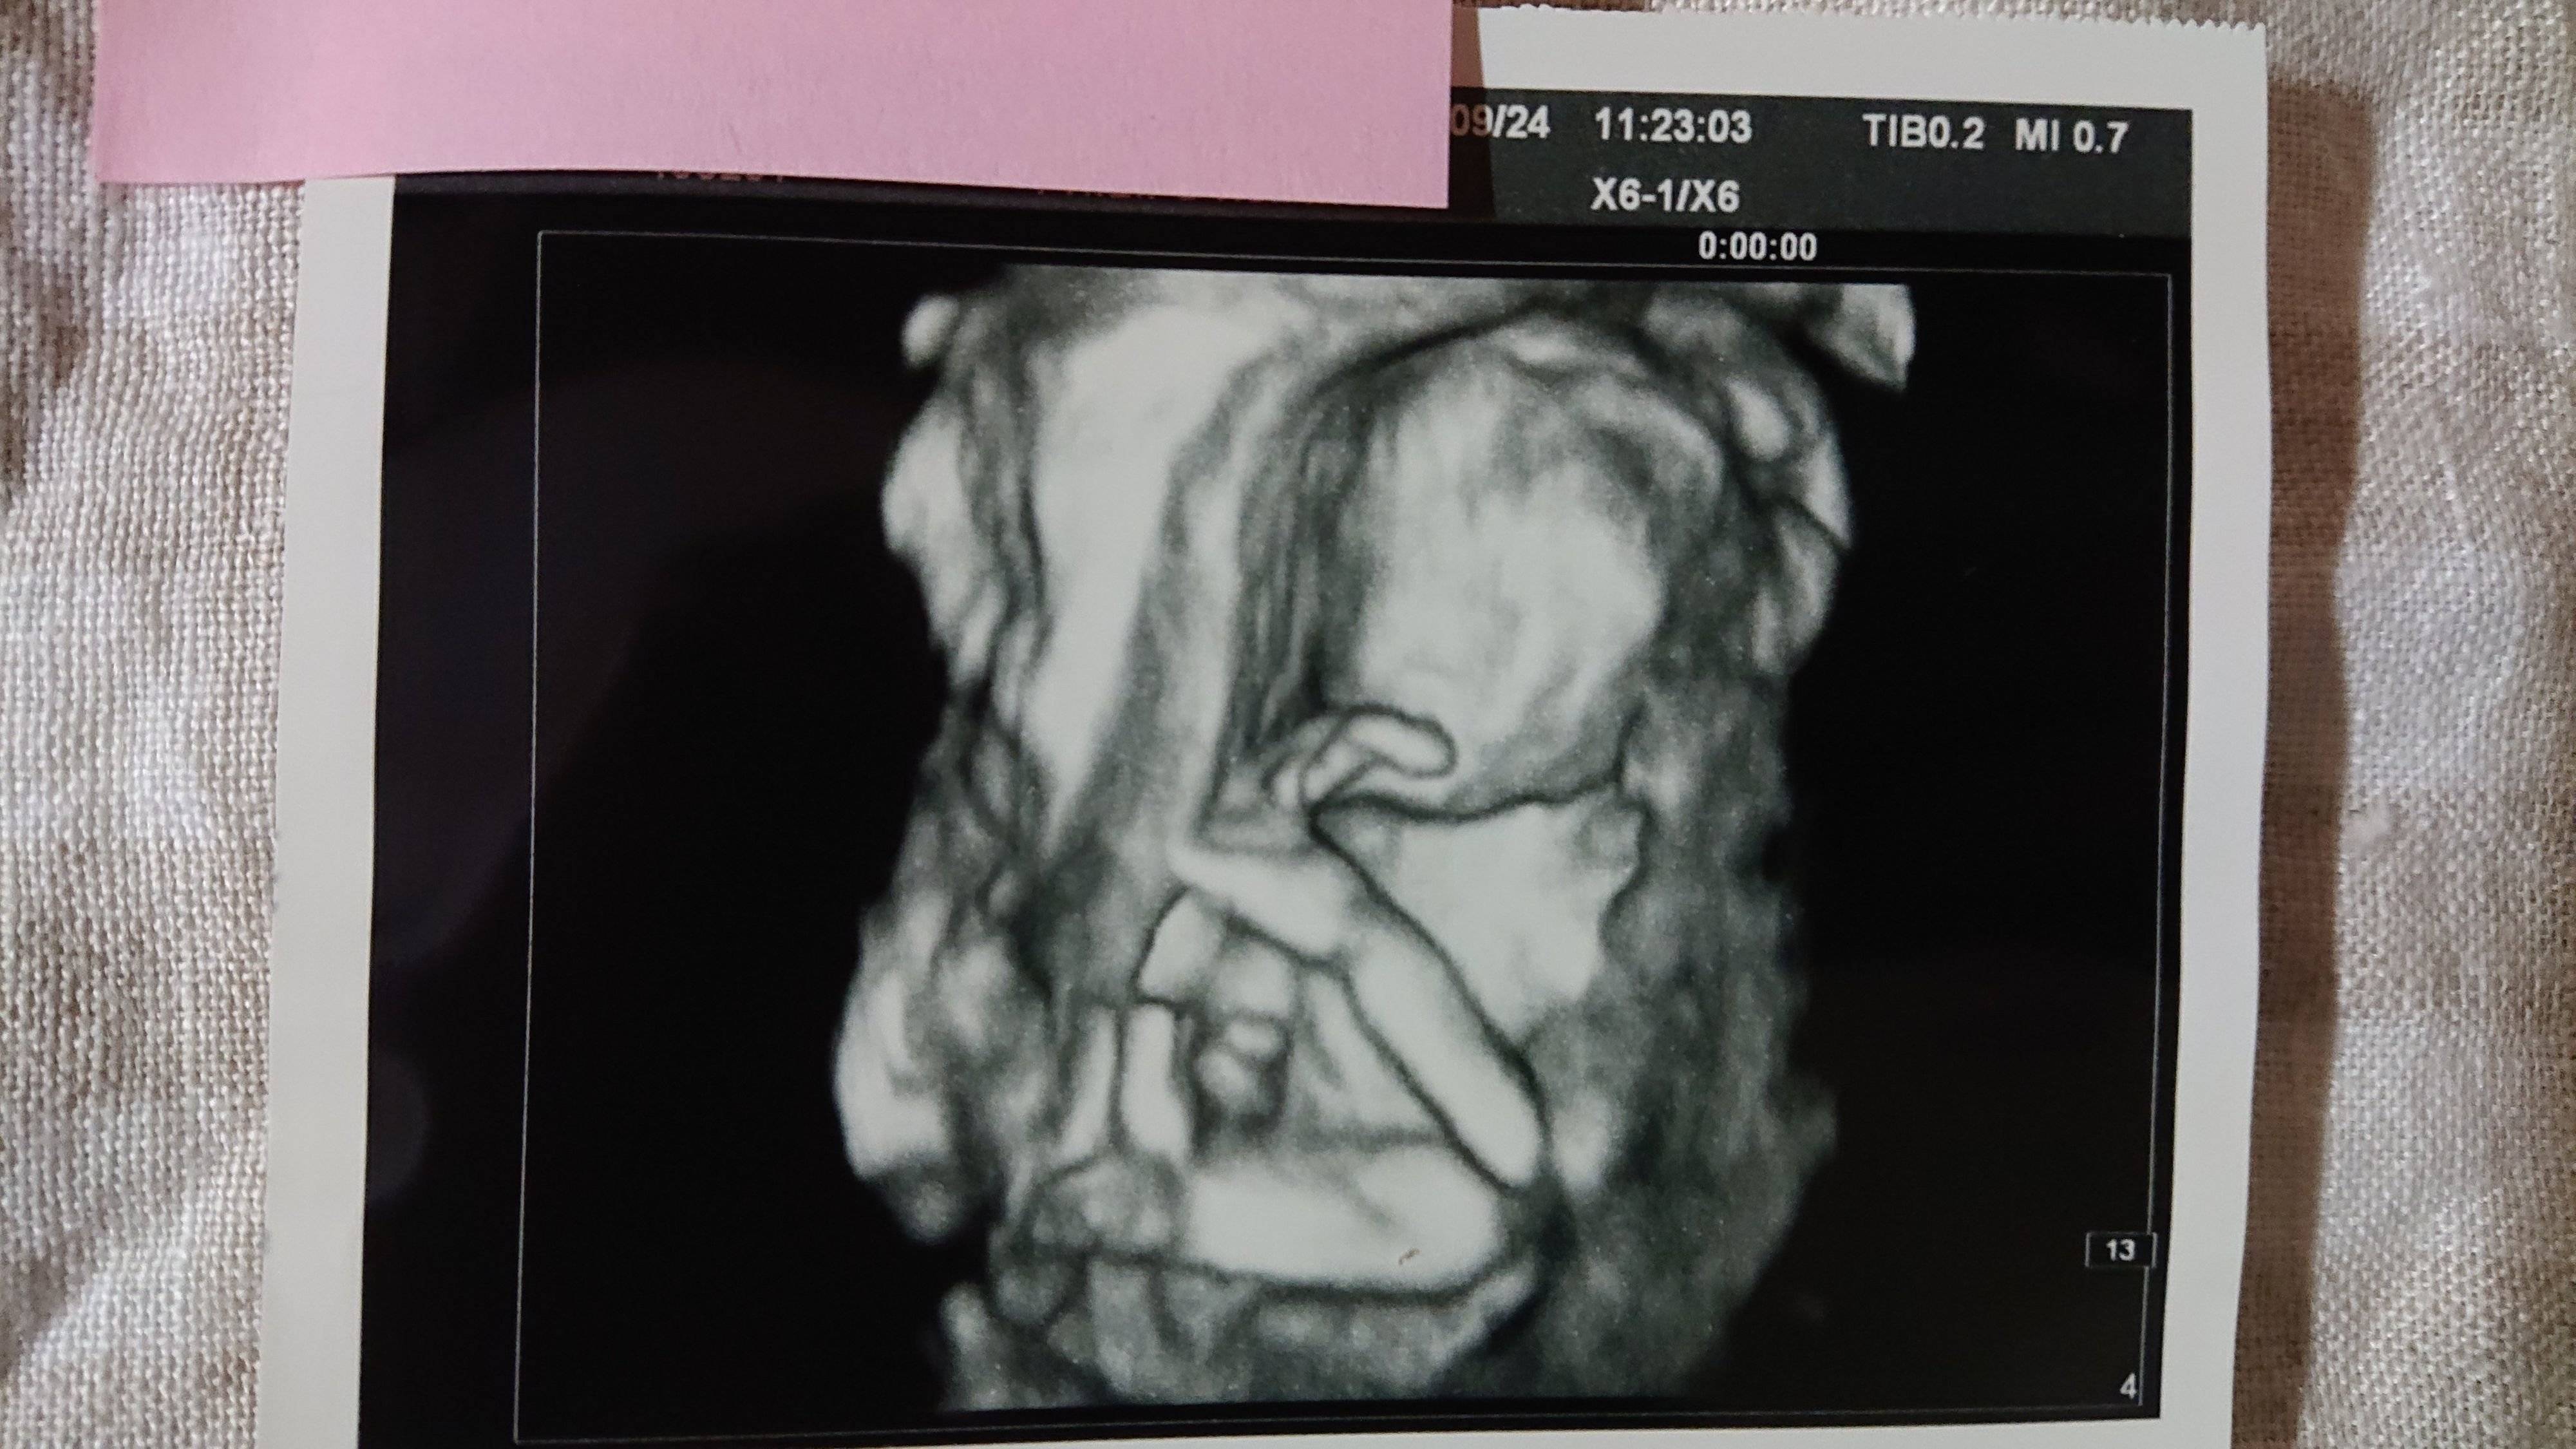

《妊娠18週目のエコー写真》

こちらは妊婦健診の日とは別に、別料金で撮影したエコー写真です。立体的でより精密に赤ちゃんをとらえることができます。専門の医師に臓器等も含め、状況をじっくり見てもらったところ、「異常なし」とのことでホッと一安心。妊婦健診の時に、「たぶん女の子かな」とは言われていましたが、ここで性別も「女の子」とほぼ確定状態になりました。